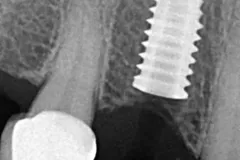

Paciente femenina de 56 años, se presenta a la consulta con puente dental desajustado, con restos alimenticios impactados, se decide realizar un corte de la estructura metálica-porcelana, para conservar piezas restauradas adyacentes, y se coloca un implante dental Marca SIN Implant, realizando provisional para carga inmediata, se espera el proceso de Osteointegración de 4 meses, se observa perfil de emergencia gingival apto, y se procede con la colocación de la corona en Zirconio.